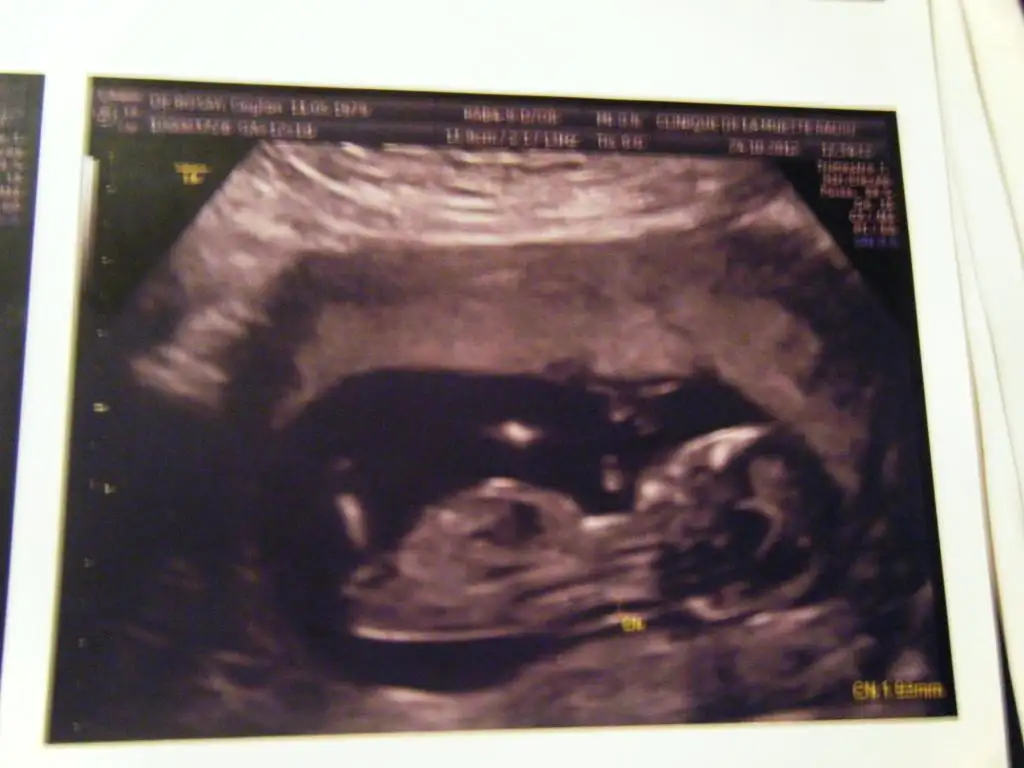

orkidem geçen eklemiştim ama tam popo tarafını ekleyememiştim doktor kız gibi ama şuan belli olmaz dedi ilerleyen haftalarda belli olur dedi

orkidem bide bu ayrıntılı ultrason resmi :) gıcık oldum doktora yaaaa sinir etti beni kızda olabilir erkekte olabilir diyooo ben ikisinede razıyım ama insan ona göre kıyafet bakıp mutlu olmak istiyo işin yoksa habire bi kız bi erkek şeylerine bak sence ben hangi renk kıyafetler bakmalıyım orkidemmm nolur kesin konuşşşş bayram bayram sevinçli geçsin

evet canim bebegin kiz gibi %60 kiz baska yokmu[/QUOTE]

demek iki kızım olucak :)))) başka fotoğraf yok yukarıya dogru olunca erkek olmuyomuydu :)

canim gecen popo kismi kesiktii alt tarafi gorememistim ama simdi farkettiysenn altta uzanan bi cikinti var

dr dur tabii daha iyi bilir ama bana kiz gibi geldi

zaten dikey olupta kiz cikan hic gormedim ama yattay olupta erkek olan cokk